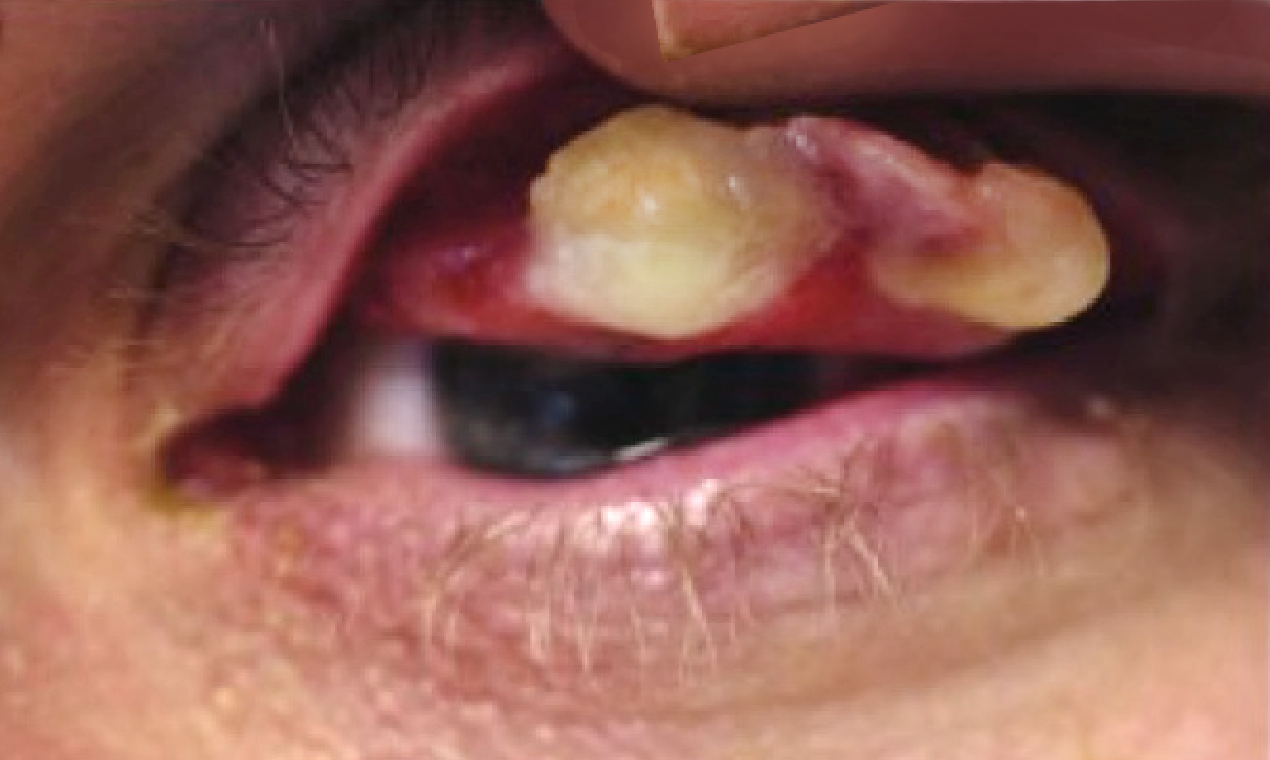

Ligneous conjunctivitis caused by congenital plasminogen deficiency type 1, manifesting as an eye lesion, prior to treatment

Fibrin-rich wood-like lesions on the conjunctiva; thickened, white, avascular4,5*

Watery, stringy pseudomembranous mass4,5*

Pseudomembranous conjunctivitis caused by plasminogen deficiency type 1, with a watery and stringy appearance